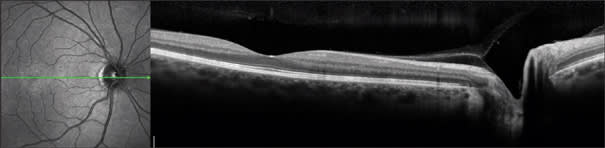

Optical coherence tomography is analogous to ultrasound imaging and radar in that they are all based on measuring the delay of a reflected radiation. So ultrasound terms such as A-scan, B-scan and C-scan have exact analogs in OCT. In ultrasound, A-scan refers to the oscilloscope display where the vertical dimension is used to display amplitude and the horizontal dimension represents the echo delay. In OCT, A-scan can also be taken as the abbreviation for axial scan, representing reflected optical amplitude along the axis of light propagation. Ultrasound B-scan referred to the cathode ray tube display where the brightness represents the amplitude of echoes. In OCT, a B-scan refers to the cross-sectional image where the amplitudes of reflections are represented in a gray scale or a false-color scale. In ultrasound, a C-scan refers to a section across structures at an equal echo delay (depth). In OCT, a C-scan refers to a section across structures at an equal optical delay. In the eye, the C-scan also conveniently corresponds to the coronal section. With FD-OCT, C-scans are synthesized from the 3D dataset. In retinal imaging, it is actually more useful to modify the C-scan to cut across a surface reference to the retinal pigment epithelial surface (Figure 7) or the inner retinal surface.

Figure 7. C-scan (upper-left) along the retinal pigment epithelium baseline (see upper-right and lower-left B-scans) helps one visualize the extent of drusenoid pigment epithelial detachment in an eye with age-related macular degeneration. The Optovue RTVue FD-OCT system was used.